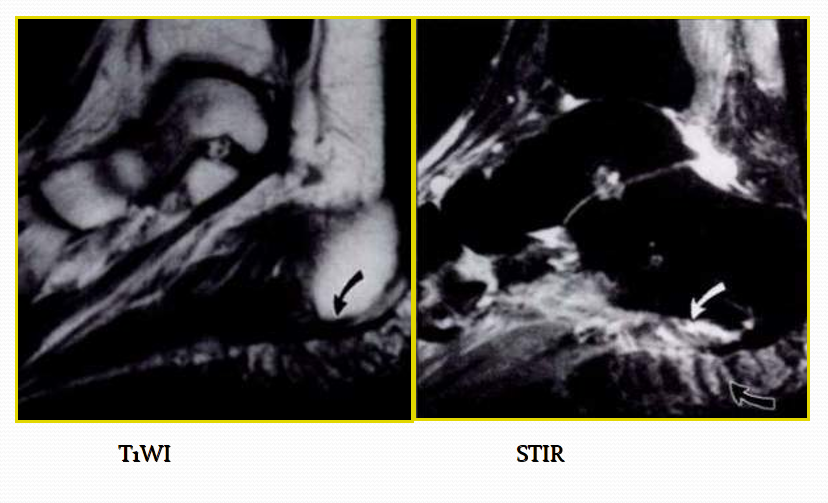

MR表现:

• 三角籽骨或距骨后三角结构模糊和变形,T1WI信号降低, T2WI信号升高

• 周围脂肪水肿

• 屈踇趾长肌腱信号升高,见鞘膜积液

• 胫骨后下跟骨上缘骨结构形态变化和信号异常。

• 三角籽骨和距骨退行性囊变